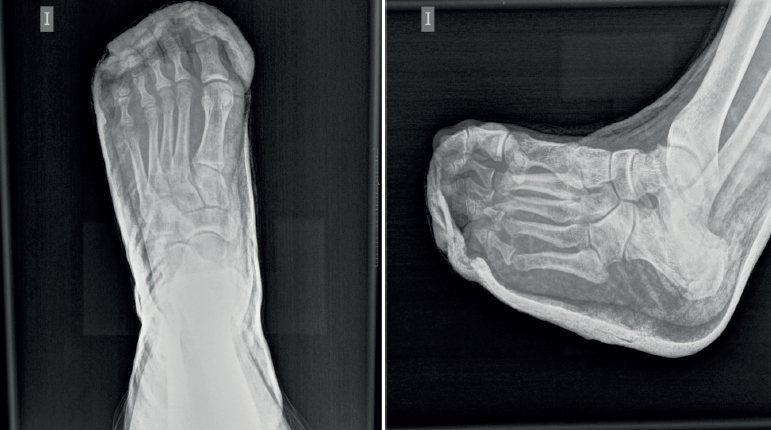

Se realizó reducción cerrada inmediata de las luxaciones con anestesia troncular por vía dorsal con mepivacaína en el segundo, el tercer y el cuarto espacios intermetatarsianos distales. La maniobra realizada fue tracción, medialización y presión en dirección dorsal-plantar de la falange proximal de cada uno de los dedos, desde el tercero hasta el quinto. Posteriormente, se comprobó clínicamente la estabilidad satisfactoria de las articulaciones metatarsofalángicas implicadas. Se procedió a una inmovilización con férula posterior suropédica con extensión hasta los dedos. Por último, se verificó mediante radiografía en proyecciones dorsoplantar y oblicua la correcta reducción de las articulaciones metatarsofalángicas, sin lesiones óseas asociadas ni aumento del espacio articular metatarsofalángico por interposición de tejidos blandos (Figura 2). La inmovilización enyesada y la descarga de la extremidad inferior izquierda se mantuvieron durante 3 semanas, iniciándose a continuación la carga.